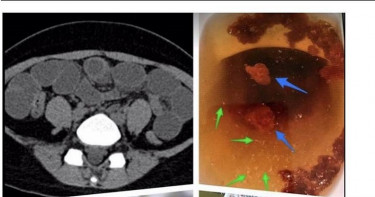

不少長輩缺乏用藥觀念,不管是錯誤的吃藥或是有病卻不吃藥的狀況相當常見,就有一名阿公因見9月大的幼童腹瀉哭不停,他竟然自作聰明把自己的止瀉藥,拿給只有9個月大的小孫子吃,以為只要剝一半小朋友就能吃,沒想到卻釀成大禍,孫子的腸子差點被撐爆。台灣兒科醫學會認為兒童就算只有腹痛、嘔吐,背後的原因也是五花八門。(示意圖/翻攝自pixabay)台灣兒科醫學會近日召開記者會,反對健保考慮取消兒童指示藥的給付。醫學會理事長李宏昌表示,兒童就算只有腹痛、嘔吐,背後的原因也是五花八門。並舉例一位阿公因見9個月大的孫子腹瀉,竟然將自己的止瀉藥剝半餵給小孫子吃,就這樣一次吃半顆還吃了4次,結果孫持出現腹脹、麻痺性腸梗阻、嗜睡和噁心嘔吐等症狀,趕緊送急診才找出腹瀉原因,是因沙門氏菌腸炎併發腸阻塞。因此台灣兒科醫學會更認為必須對症下藥,根據孩童年齡、體重做最適當的藥物劑量調整。